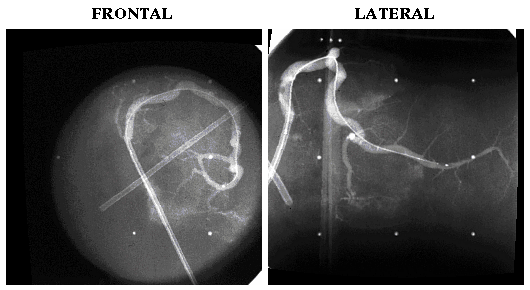

Angiograms of Cadaveric Pig RCA with IVUS Catheter